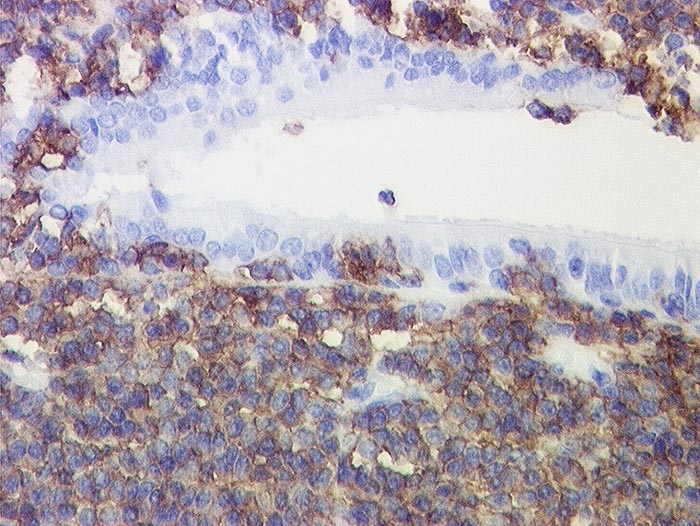

PathoPic – image database / PathoPic ID 1010 - Marginalzonenlymphom vom MALT Typ: Lymphoepitheliale Läsion

Marginalzonenlymphom vom MALT Typ: Lymphoepitheliale Läsion

In der Bronchialschleimhaut Gruppen von mehr als 5 Lymphomzellen. Diese reagieren positiv mit dem B-Zell Marker CD20. Die subepithelial gelegenen Lymphomzellen reagieren ebenfalls positiv.

Histologie

Immunhistochemie

CD20 (L26)